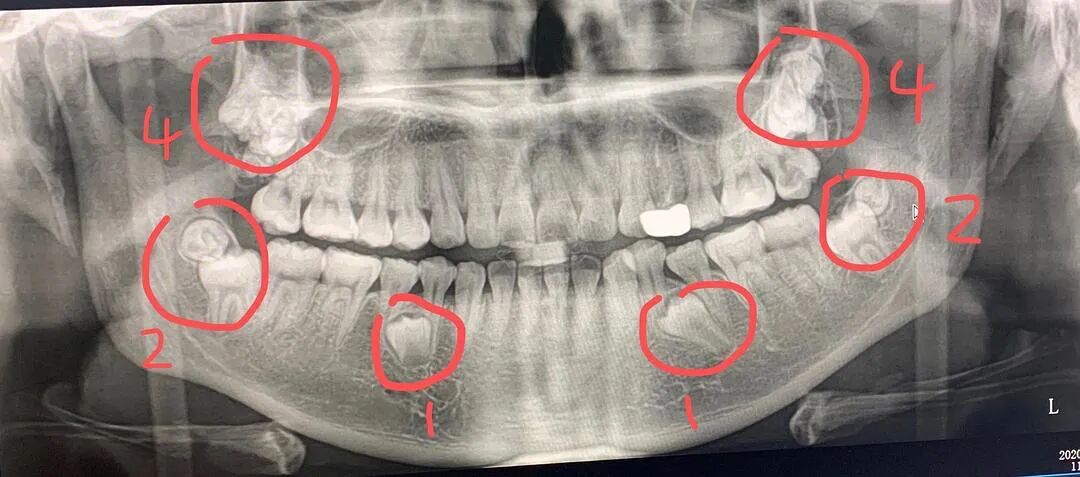

数量标记图

目前除了下面两颗埋伏牙,十二颗智齿全拔除干净了。

左下部位拔除的两颗

右边上下一起拔除的五颗

左上部位拔除的四颗